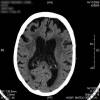

AVC amplio de territorio de A. cerebral media